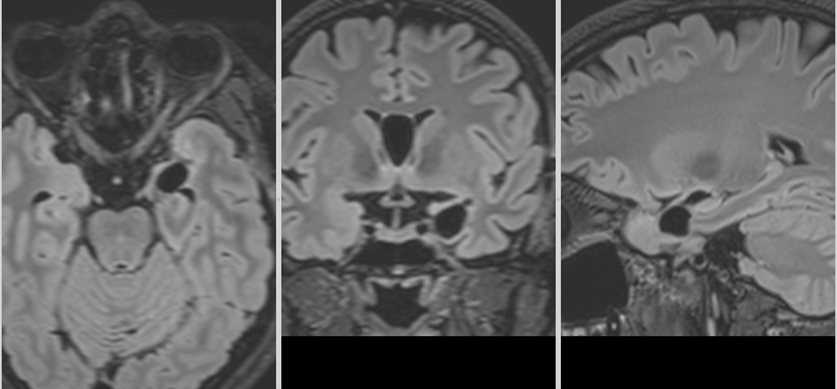

Primele imagini RMN realizate imediat după intervenție au confirmat absența complicațiilor. Câteva săptămâni mai târziu, un nou control imagistic a arătat clar rezultatul: tumora fusese îndepărtată în totalitate.

Investigațiile următoare, întâi peste 3 luni apoi peste încă un an au confirmat: nici o urmă de rest sau recidivă tumorală.

La aproape 3 ani de la operație, fără crize epileptice, fără deficite neurologice și cu un RMN curat putem considera că pacienta este vindecată.